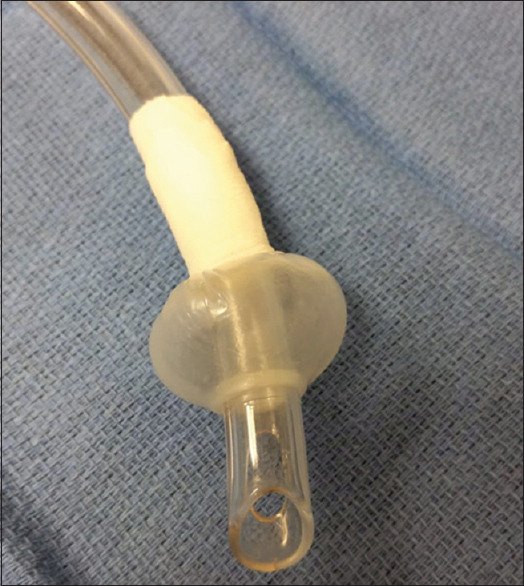

摘要:全喉切除术后气道给围手术期麻醉管理带来了挑战。虽然支气管内插管是一种常见的并发症,但低位造口可能会增加这种风险。此外,造口靠近胸骨正中切口也增加了手术和气道管理的复杂性。本报告重点介绍了一例低位造口患者进行支气管内插管的病例,该患者前来接受冠状动脉旁路移植手术。由于造口位于胸骨上缘,因此需要在术中进行创新,以防止气管内插管,同时保持在手术视野之外。这种创新在紧急手术情况下可能很有用。

Abstract: The post-total laryngectomy airway poses perioperative challenges to anesthesia management. While endobronchial intubation is a cited complication, a low-lying stoma may increase this risk. Furthermore, the stoma's proximity to a median sternotomy increases surgical and airway management complexity. This report highlights a case of endobronchial intubation in a patient with a low-lying stoma who presented for coronary artery bypass graft. With a stoma at the upper border of the sternum, intraoperative innovation was required to prevent endobronchial intubation while remaining out of the surgical field. This innovation may be useful in urgent surgical situations.